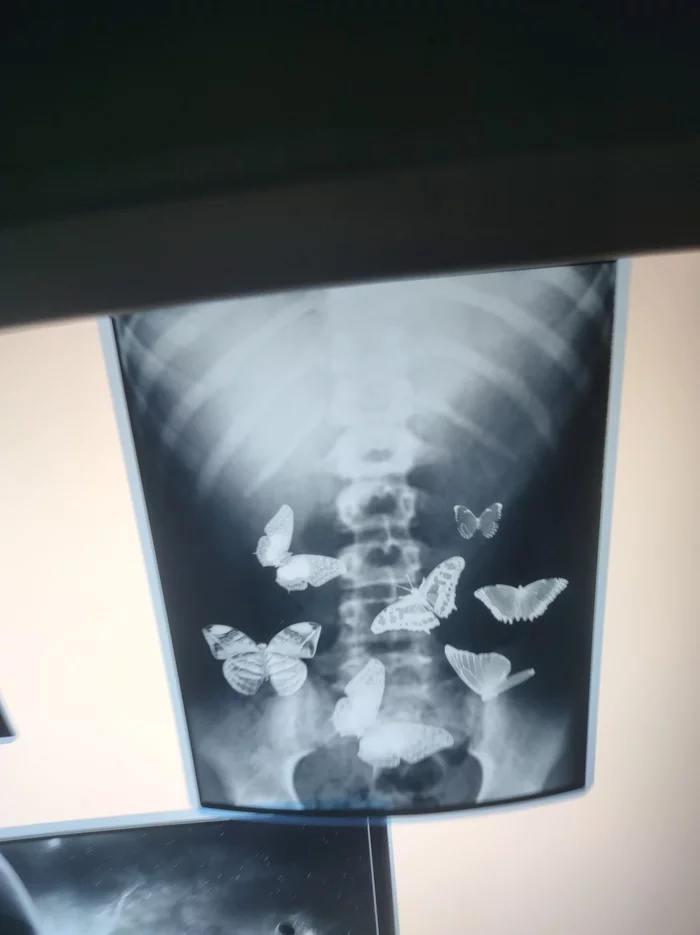

Смешные картинки и мемы ко Дню рентгенолога